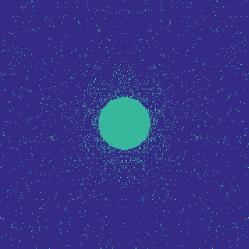

Figure 1 illustrates the best performing randomized indices and our learned set of indices in the plane of the -space. Both the variable density approach [14] and our learning-based approach concentrates its sampling budget on the low frequencies, however the latter is endowed with the capability to adapt its frequency selection to the frequency content of the training signals instead of assuming a circularly symmetric selection.